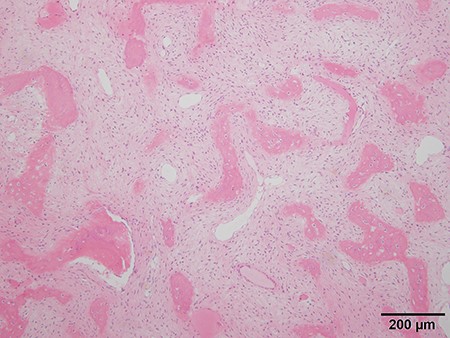

Because differential diagnoses included malignant transformation from fibrous dysplasia based on the clinical course and imaging, a CT-guided biopsy was performed. Tissue was obtained from various areas with differing contrast effect on MRI. Despite no histological evidence of malignancy, signs of fibrous dysplasia such as irregular osseous trabeculae of immature bone with no osteoblastic rimming were observed. Accounting for possibly insufficient samples, incisional biopsies of the right seventh and ninth ribs were performed. The results showed fibrous dysplasia signs similar to those that were shown by the CT-guided biopsy, and the patient was preoperatively diagnosed as fibrous dysplasia (Fig. 5).

Histologic analysis of the biopsy shows characteristics of fibrous dysplasia with irregular osseous trabeculae of immature bone with no osteoblastic rimming.